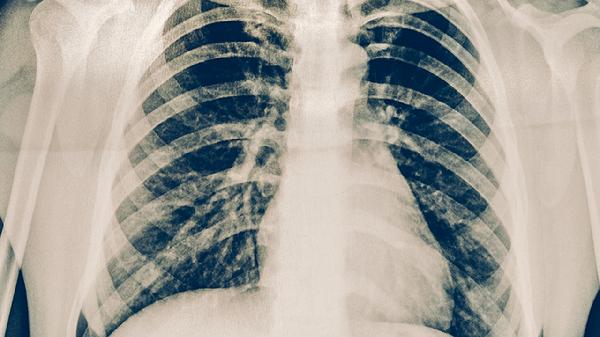

對(duì)于藥物治療無(wú)效或出現(xiàn)嚴(yán)重并發(fā)癥的肺結(jié)核患者,可能需要手術(shù)治療。常見(jiàn)術(shù)式包括肺葉切除術(shù)、空洞引流術(shù)等。手術(shù)可清除病灶,減少結(jié)核桿菌數(shù)量。術(shù)后仍需繼續(xù)抗結(jié)核治療,防止復(fù)發(fā)。手術(shù)治療風(fēng)險(xiǎn)較高,需嚴(yán)格評(píng)估患者身體狀況。